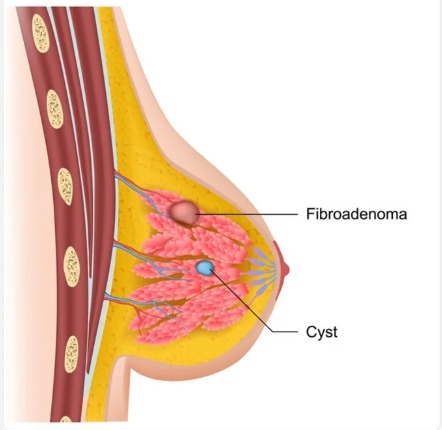

Fibroadenoma

सीने में गांठं गांठ